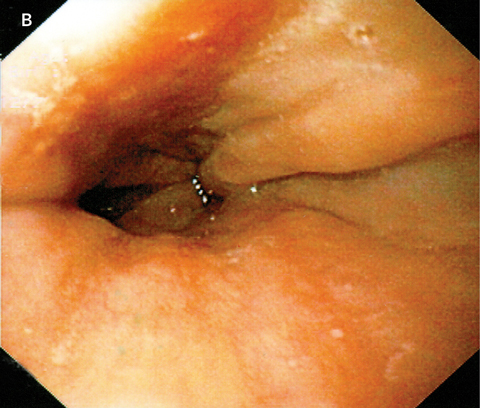

The patient was commenced on 40 mg daily of esomeprazole (a proton-pump inhibitor). Over the following week, he experienced a gradual improvement in his odynophagia and was able to return to a normal diet. Esomeprazole treatment was continued for 8 weeks and he remained asymptomatic. A repeat upper gastrointestinal endoscopy a further 2 weeks later showed complete healing of the oesophagus (Box B).